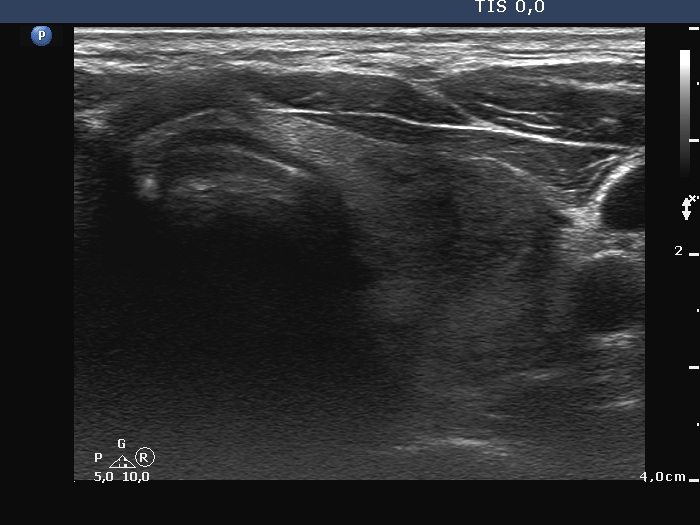

Examination a year after the first visit (third row of images):

Clinical presentation: The patient had no complaints.

Palpation: no abnormality.

Laboratory tests: TSH 1.60 mIU/L, FT4 15.6 pM/L, aTPO 12 U/mL.

Ultrasonography: The dorsal part of the right lobe remained hypoechoic. The nodule in the left lobe has increased in size and presented halo and signs of perinodular vascularity.

Cytology of the nodule resulted in benign lesion.

Suggestion: repeat examination in three years.